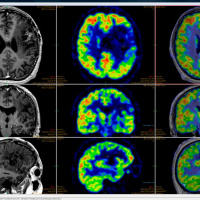

• Medical Imaging Technology - Episode 58

11/10/2017 Duration: 33min

Unless you've been pretty lucky all your life, you've probably had to rely on medical imaging at some point. That could be something simple like an x-ray for a broken arm, or something more complicated like a MRI or CAT scan. Have you ever thought about how those machines work? Photons, atoms, tungsten, H2O and giant magnets for a start! Join us to find out more!